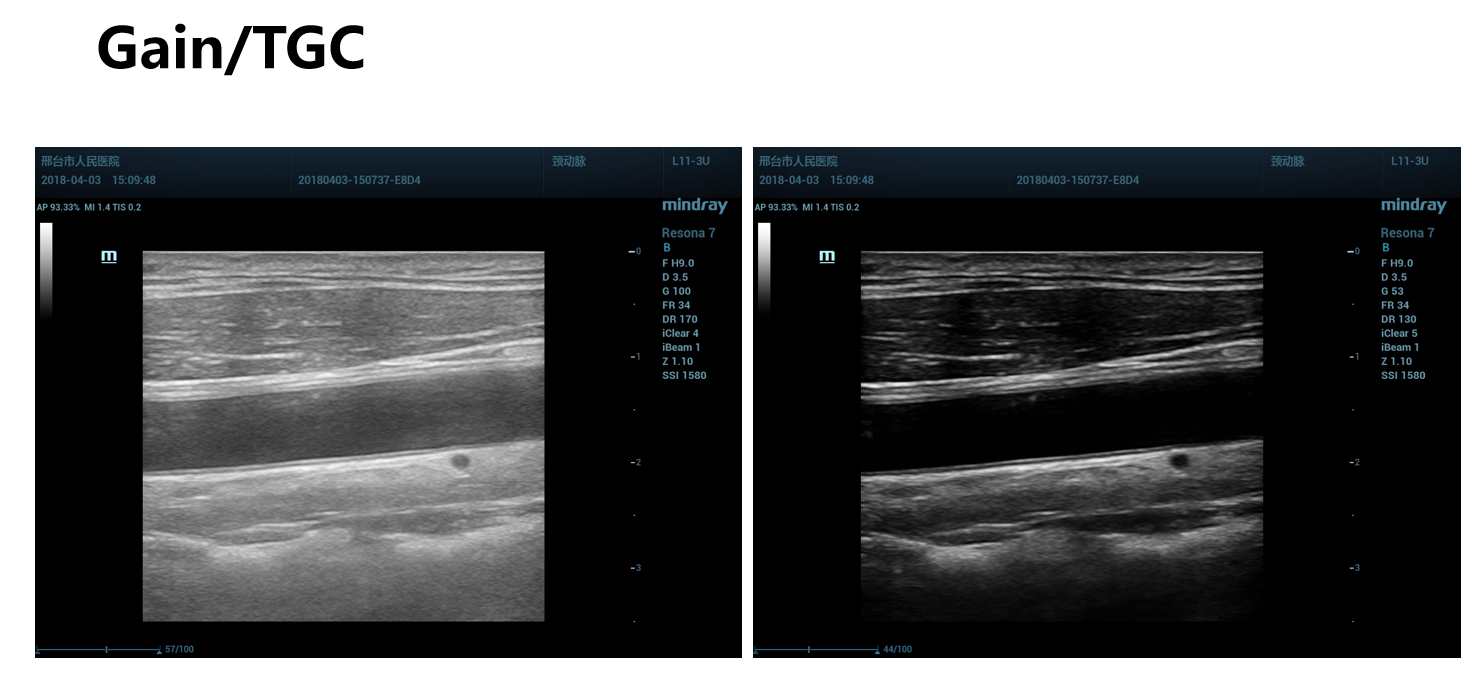

动态范围是机器对强弱信号接收和处理的范围,他显示图像的灰阶级别数,动态范围增加信息量增多,可以显示微弱的信号,使图像变得柔和,但是动态范围太大,图像发雾。动态范围减低,信息量减少,导致图像的对比度高,微弱的信号被除去,灰阶层次减少,图像相对清亮。总之,动态范围实际表现,就是图像的对比度。